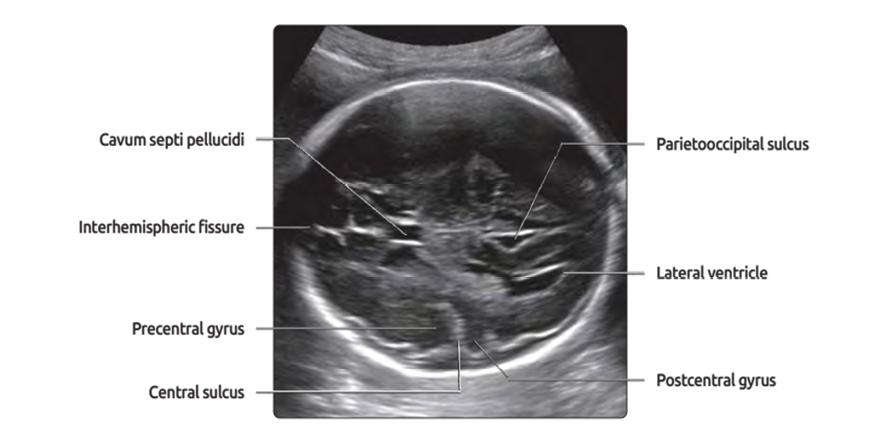

Figure 1. Trans-ventricular view [3].

The visualization of CSP is considered an integral part of the prenatal second and third trimester sonographic evaluation of the fetal neural axis [1, 2]. Also, it is critical anatomical land mark of the normal midline development of fetus’s brain [3]. The septa pellucida are two, thin translucent leaves that extend from the anterior part of the body, the genu and the rostrum of the corpus callosum to the superior surface of fornix. Fetuses begin to develop at 10–12 weeks of gestation and reach an adult form by the 17th week of gestation [4]. It should always be visible between 18-37 weeks or when the biparietal diameter measures 44-88 mm. Failure to visualize it after 37 weeks is almost certainly due to the normal obliteration if brain is otherwise normal [5, 6]. Failure to demonstrate the CSP with antenatal ultrasound is typical of many cerebral anomalies, such as holoprosencephaly, schizencephaly, agenesis of the corpus callosum and septo-optic dysplasia [7-11]. This study is novel and clinically significant because, until now, Iranian physicians have relied on CSP reference ranges derived from European or American populations, which may not accurately reflect normal fetal brain development in Iranians due to potential ethnic, genetic, or anthropometric differences. Using foreign standards risks misdiagnosis, either overestimating abnormalities in healthy fetuses or missing true anomalies. By establishing the first gestational age-specific reference ranges for CSP width in an Iranian population, this study provides locally applicable normative data, ensuring more accurate prenatal assessments. Additionally, since Iran’s legal abortion cutoff is 18 weeks and 5 days, precise CSP measurements are crucial for timely decisions and borderline values based on Western data could lead to unnecessary terminations or missed interventions.

All fetuses had normal brain scan in examination, CSP was identified on axial trans-ventricular plane and antero-posterior diameter on the inner borders of its proximal and distal bounding (inner to inner) and the length of CSP (inner to inner). The BPD and HC were measured in trans-thalamic plane in these fetuses. All these results were recorded in the information list. A polynomial regression model was used to assess the relationship between CSP width and BPD, CSP width and HC. No follow-up was considered as this study was conducted retrospectively.